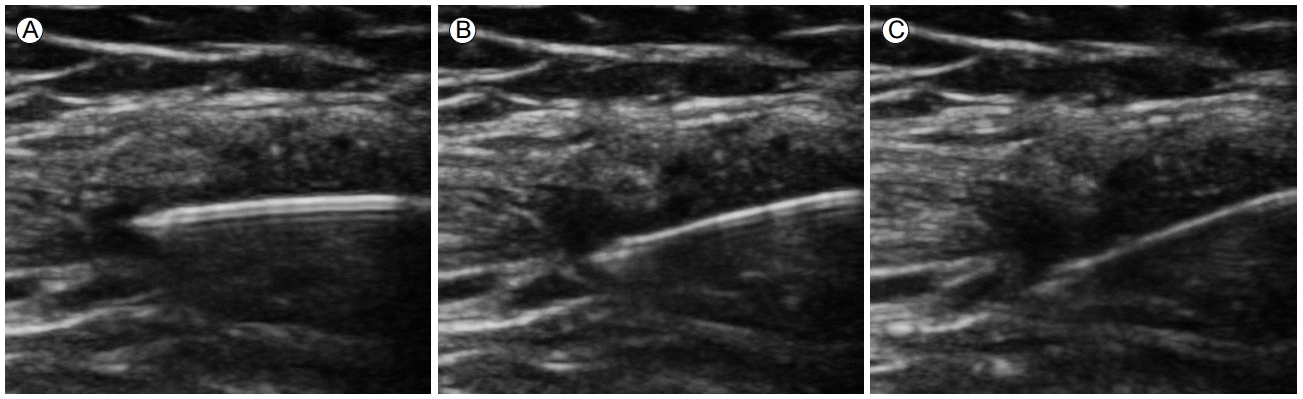

손목은 류마티스관절염이 가장 흔하게 침범하는 관절 중의 하나이다. 초음파 검사는 손목 통증과 종창의 원인이 관절내부 또는 주변의 건초염 인지를 확인하여 목표 구조물을 결정하는데 매우 유용하다. 요골수근골(radiocarpal)관절내 주사는 환자의 손목을 필로우에 올려두어 손목을 약간 굽힌 상태에서 탐촉자를 종축으로 위치한 후 lister’s tubercle 1-2 cm 원위부에서 바늘을 진입하는 방법이 있으며, 탐촉자를 손목에 횡축으로 위치한 후 요골방향에서 요골수근골 관절면에 평행하게 2nd extensor tendon compartment 아래로 통해 바늘을 진입시켜 주사하기도 한다(Fig. 6) [22].